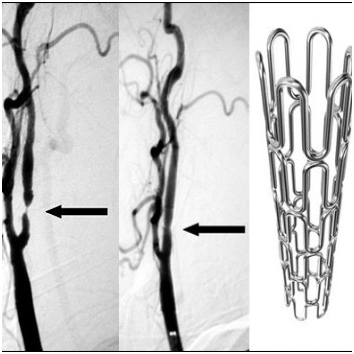

Споредбено со луѓето кои имаат нормален крвен притисок

оние

со висок крвен притисок почесто страдаат од мозочен удар. Околу 87%

од мозочните

удари се исхемични

односно

мозочни удари

кои

настануваат како резултат на стеснување или зачепување на крвните

садови во мозокок при што доаѓа до прекин на

циркулацијата во мозочното ткиво. Околу 13% од мозочните

удари се хеморагични односно настануваат како резултат на пукање на

крвен сад во мозкот. Долго време

нелекуван

висок

крвен притисок доведува до оштетување на

зидот

на крвните садови и нивно пукање.